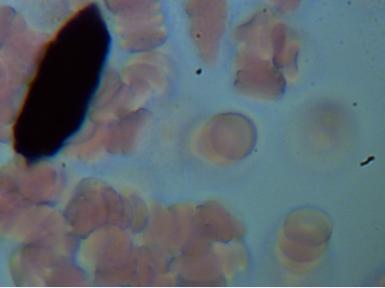

2.KRYSZTAŁY KWASÓW

Obecność kryształów soli kwasów w organizmie świadczy o jego zakwaszeniu. Sól może odkładać się w nerkach w postaci piasku lub kamieni , w stawach powodując stan zapalny i zwyrodnienia oraz w wielu innych narządach.

3.KRYSZTAŁY KWASU ORTOFOSFOROWEGO - którego obecność świadczy o zaburzeniu równowagi kwasowo-zasadowej. Wapń jest jednym z pierwiastków , które organizm wykorzystuje do przywrócenia tej równowagi . Jeżeli zakwaszenie jest duże powstają coraz większe kryształy , w konsekwencji mamy problemy z paznokciami, włosami , zębami oraz wzrasta zagrożenie osteoporozą.